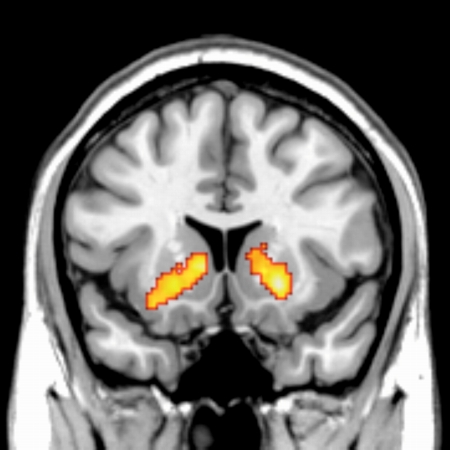

金銭報酬と社会的報酬による基底核の活動

報酬は全ての生物の行動決定に影響を及ぼす要因である。ヒトにおいては食べ物などの基本的報酬の他に,他者からの良い評判・評価というような「社会的報酬」が行動決定に大きな影響を持つということが,社会心理学などの分野の研究から知られている。しかし,今までそのような社会的報酬が,その他の報酬(例えば,食べ物,お金)と同じ脳部位で処理されているのかはわかっていなかった。この研究では,他者からの良い評価を社会的報酬として与えた場合は,金銭報酬を与えた時と同じ報酬系の脳部位が,同じ活動パタンを示すということを見出した。他者からの評判・評価という社会的報酬が,普段の我々の社会的行動に大きな影響を持つことを考えると,この知見は複雑なヒトの社会的行動に対して神経科学的説明を加えるための重要な最初の一歩であると考えられる。